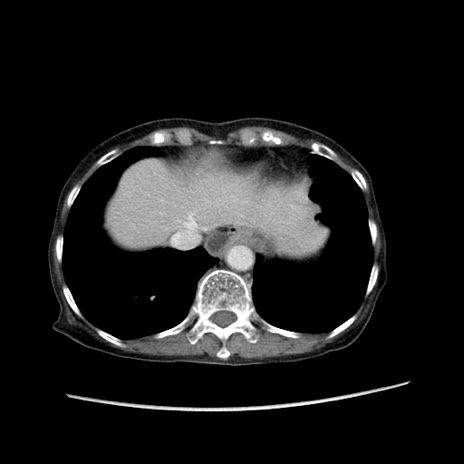

症例25(横断像)

【症例】80歳代女性

【主訴】胸のつかえ感

【現病歴】約9時間前に食後から胸のつかえた感じあり、嘔吐あり、来院。

【既往歴】胃癌(全摘)、胆摘、虫垂炎

【身体所見】心窩部に圧痛あり、反跳痛なし。

【データ】WBC 5700、CRP 0.05